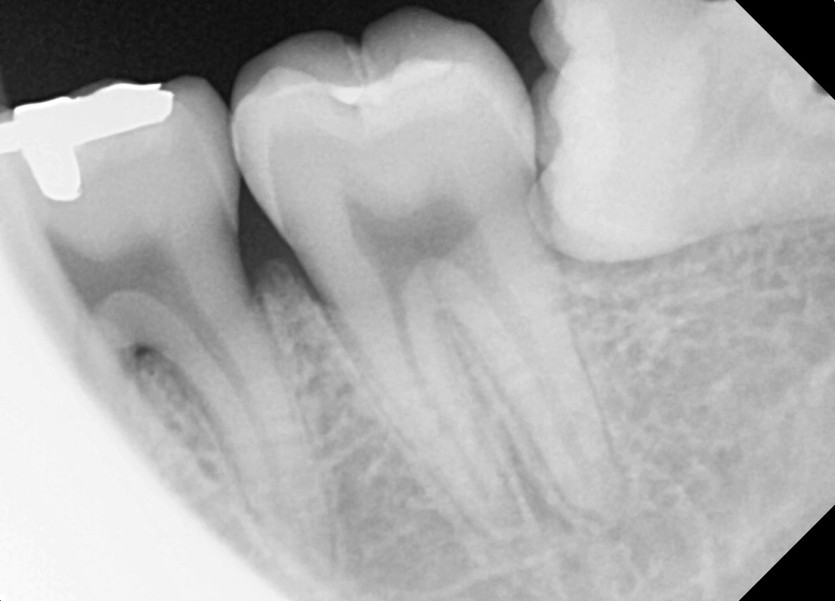

#28,38 사랑니 발치

구강 외과 전문의가 당일 발치했습니다.